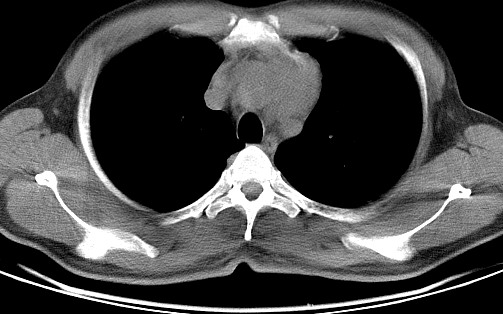

男   40   反复腹痛入院行彩超检查示胸骨右缘4、5肋间不均质回声团

淋巴瘤:前纵隔可见多组肿大的淋巴结,部分融合,有液化坏死

莲蓬籽征  考虑淋巴瘤